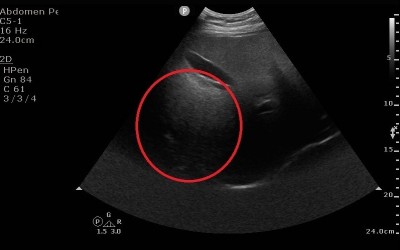

台中50歲林先生是B型肝炎帶原者,平時固定在診所抽血檢查追蹤,多年來數據正常,日前因血液中肝癌的腫瘤標記指數異常,轉介至醫院安排腹部肝臟超音波檢查,赫然在肝臟發現3公分大腫瘤,已是第2期肝癌,醫師提醒B型肝炎患者,要定期接受腹部超音波檢查,避免小病拖成大病。

台中50歲林先生是B型肝炎帶原者,平時有固定在診所抽血檢查追蹤,多年來數據都正常,直到日前因血液中肝癌的腫瘤標記指數異常,轉介至醫院進一步安排腹部肝臟超音波檢查,赫然在肝臟發現3公分大腫瘤,且已是第2期肝癌,醫師提醒B型肝炎患者,也要定期接受腹部超音波檢查,避免小病拖成大病。